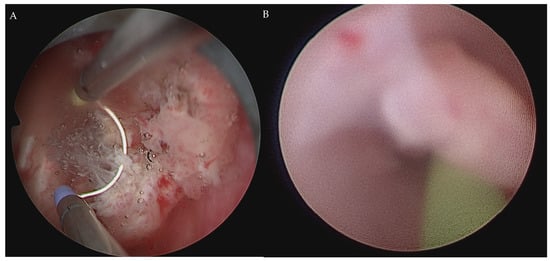

2.2. Robot-Assisted CUTE